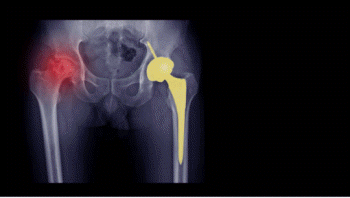

- X-ray(방사선사진) : 후반부 이상 감지

2. 수술적 치료

- 관절 치환술(인공관절) : 손상 부위가 넓을 때 주로 시행

수술 선택은 연령, 괴사 범위, 증상 정도에 따라 결정